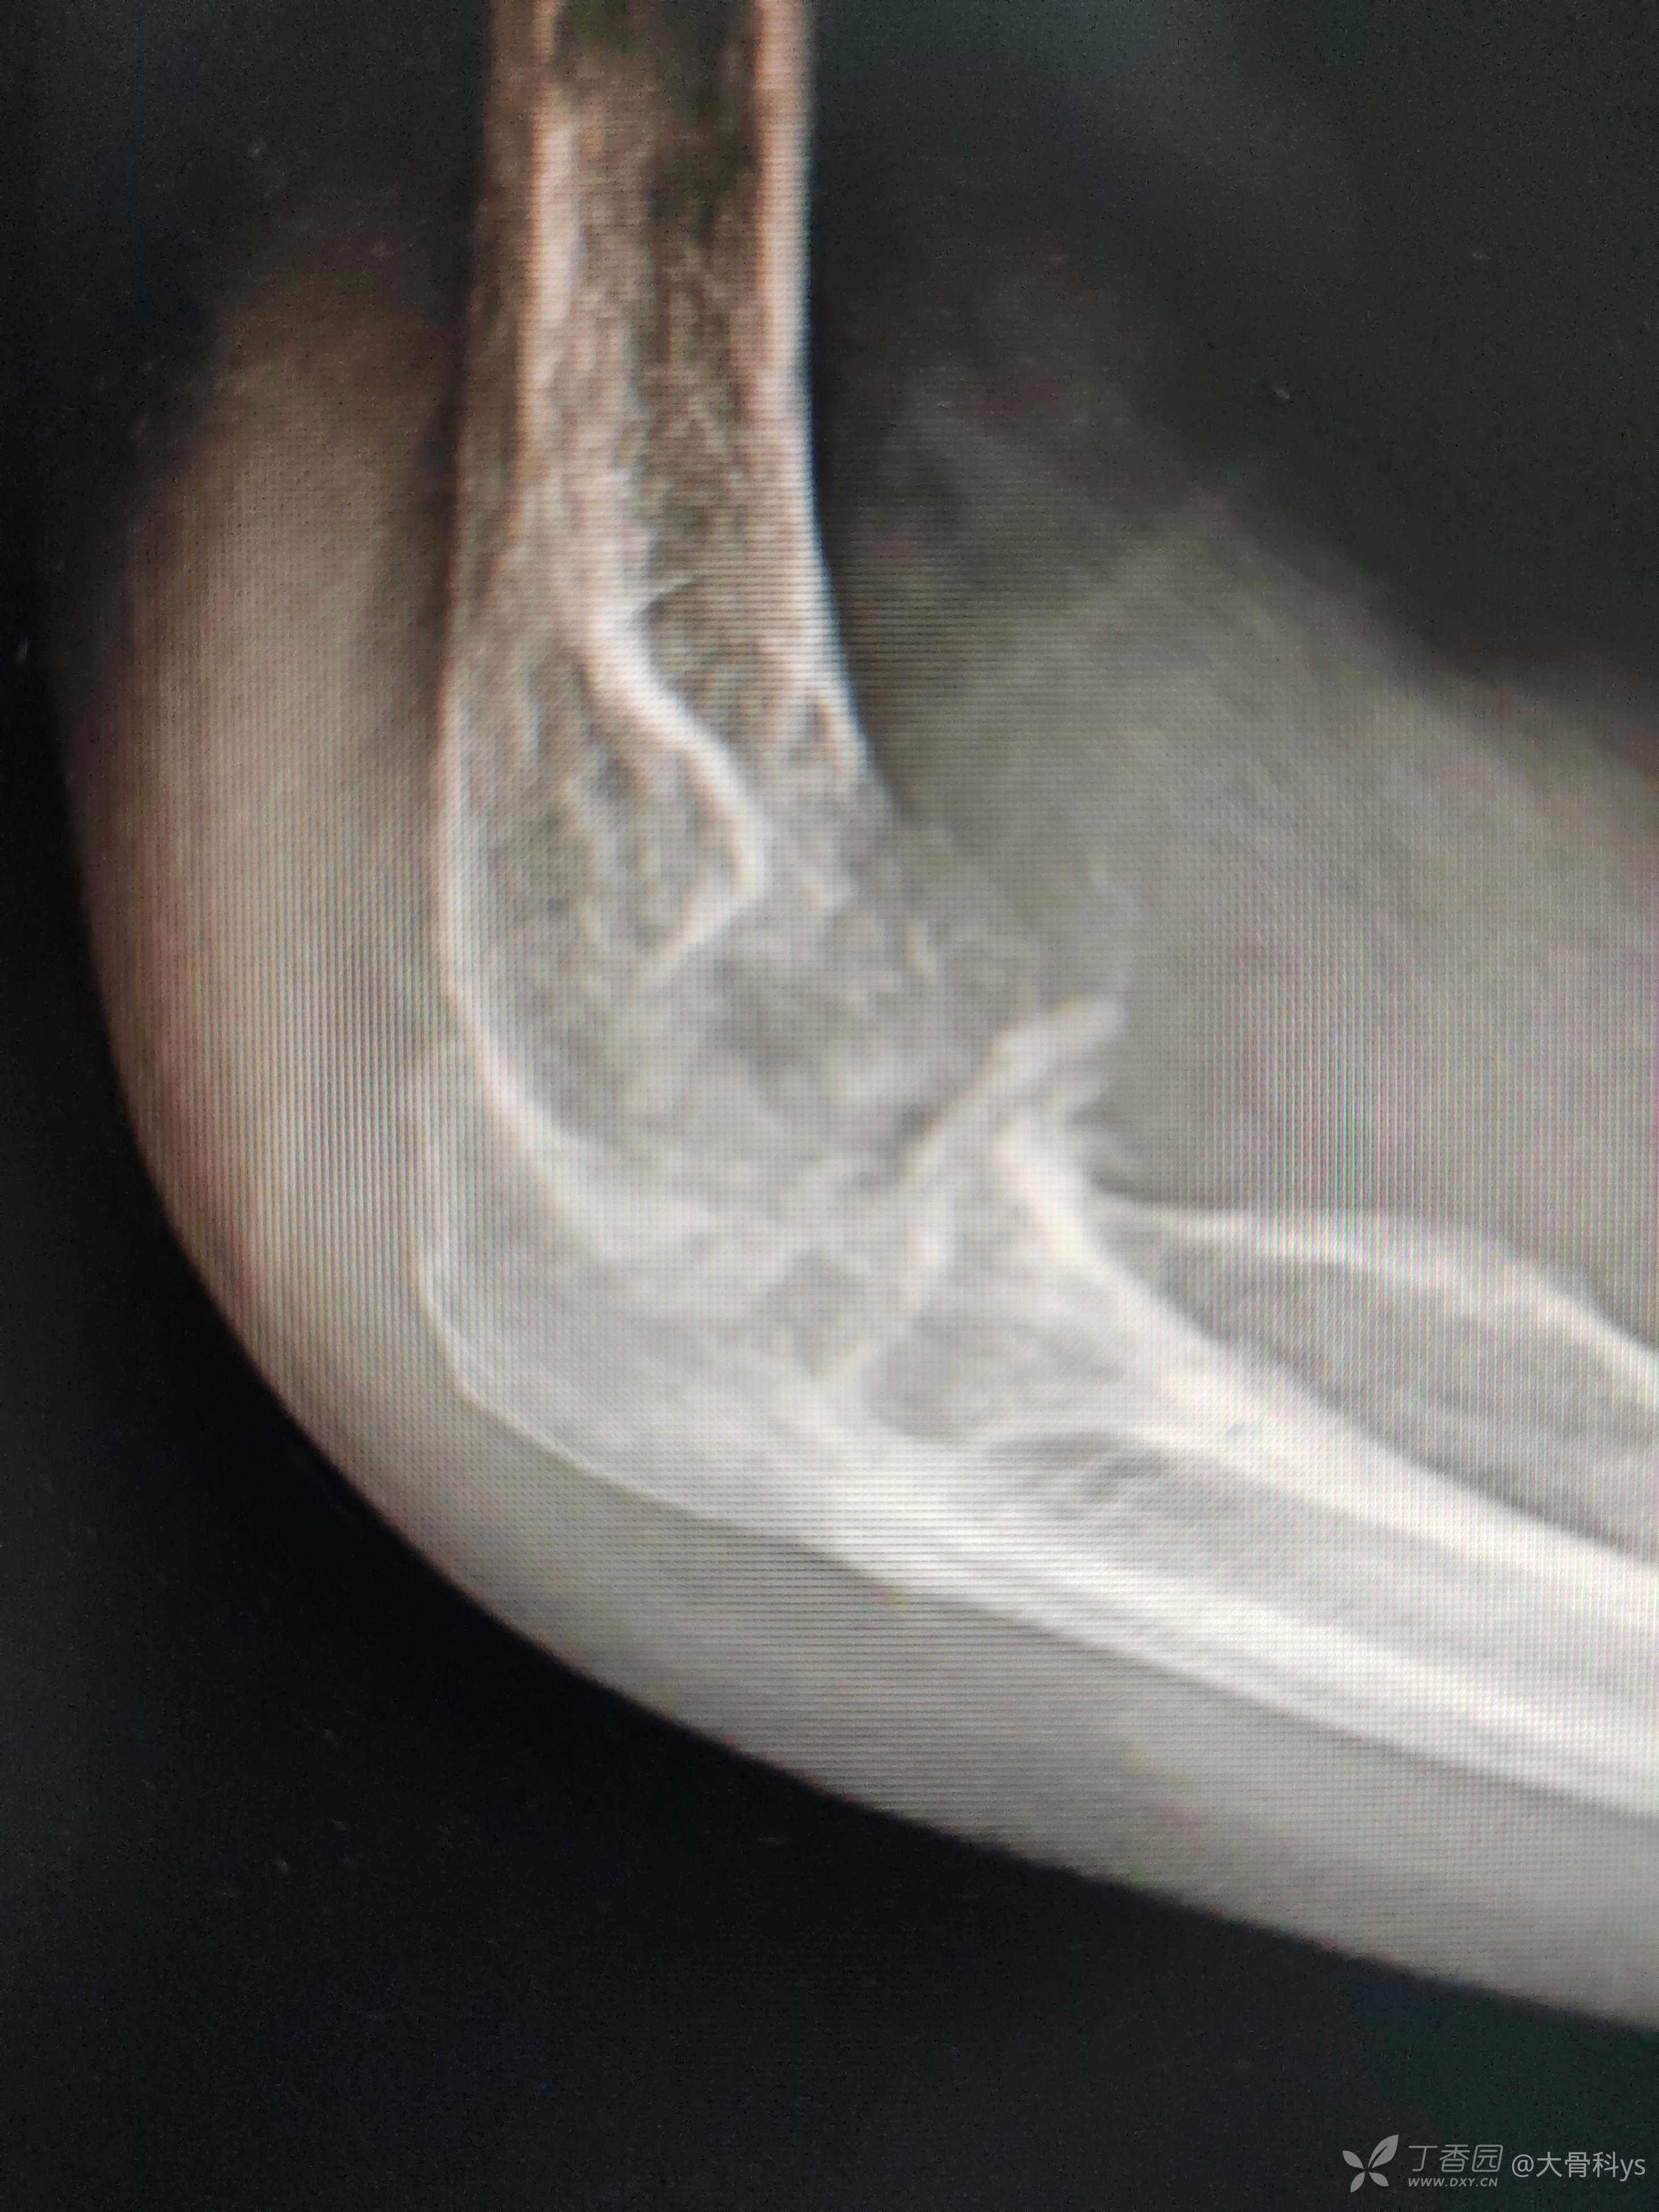

影像学资料

双肺CT检查提示双肺广泛性弥漫性改变:结核?尘肺?